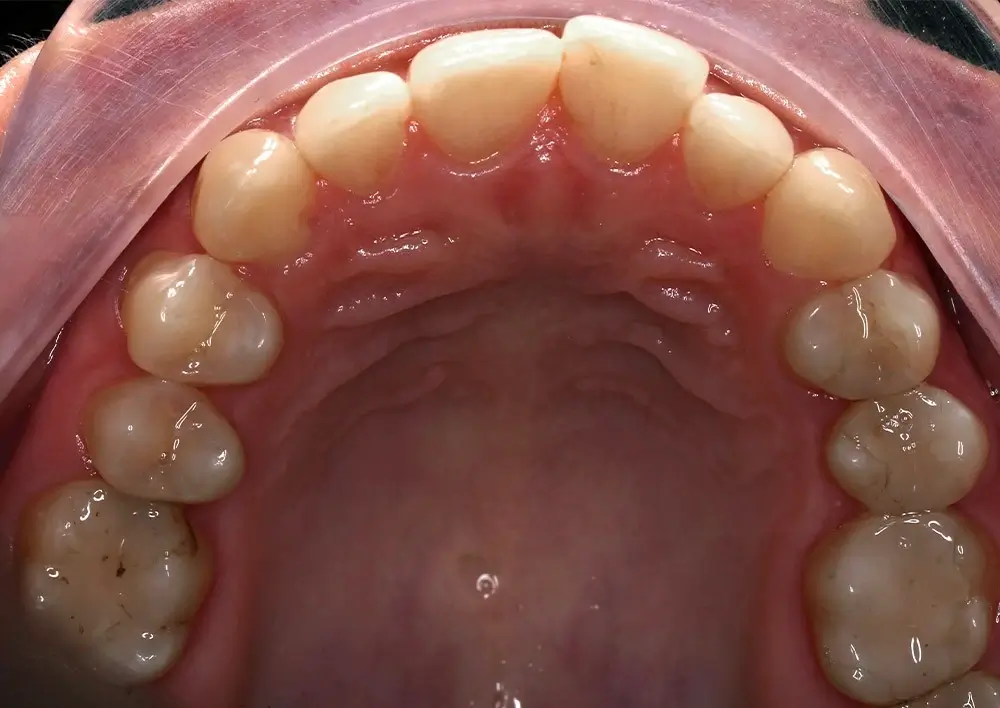

Кейс 13

Булгач (Мочалова) Галина Игоревна

Количество кап ВЧ 19

Количество кап НЧ 24

ДО

ПОСЛЕ